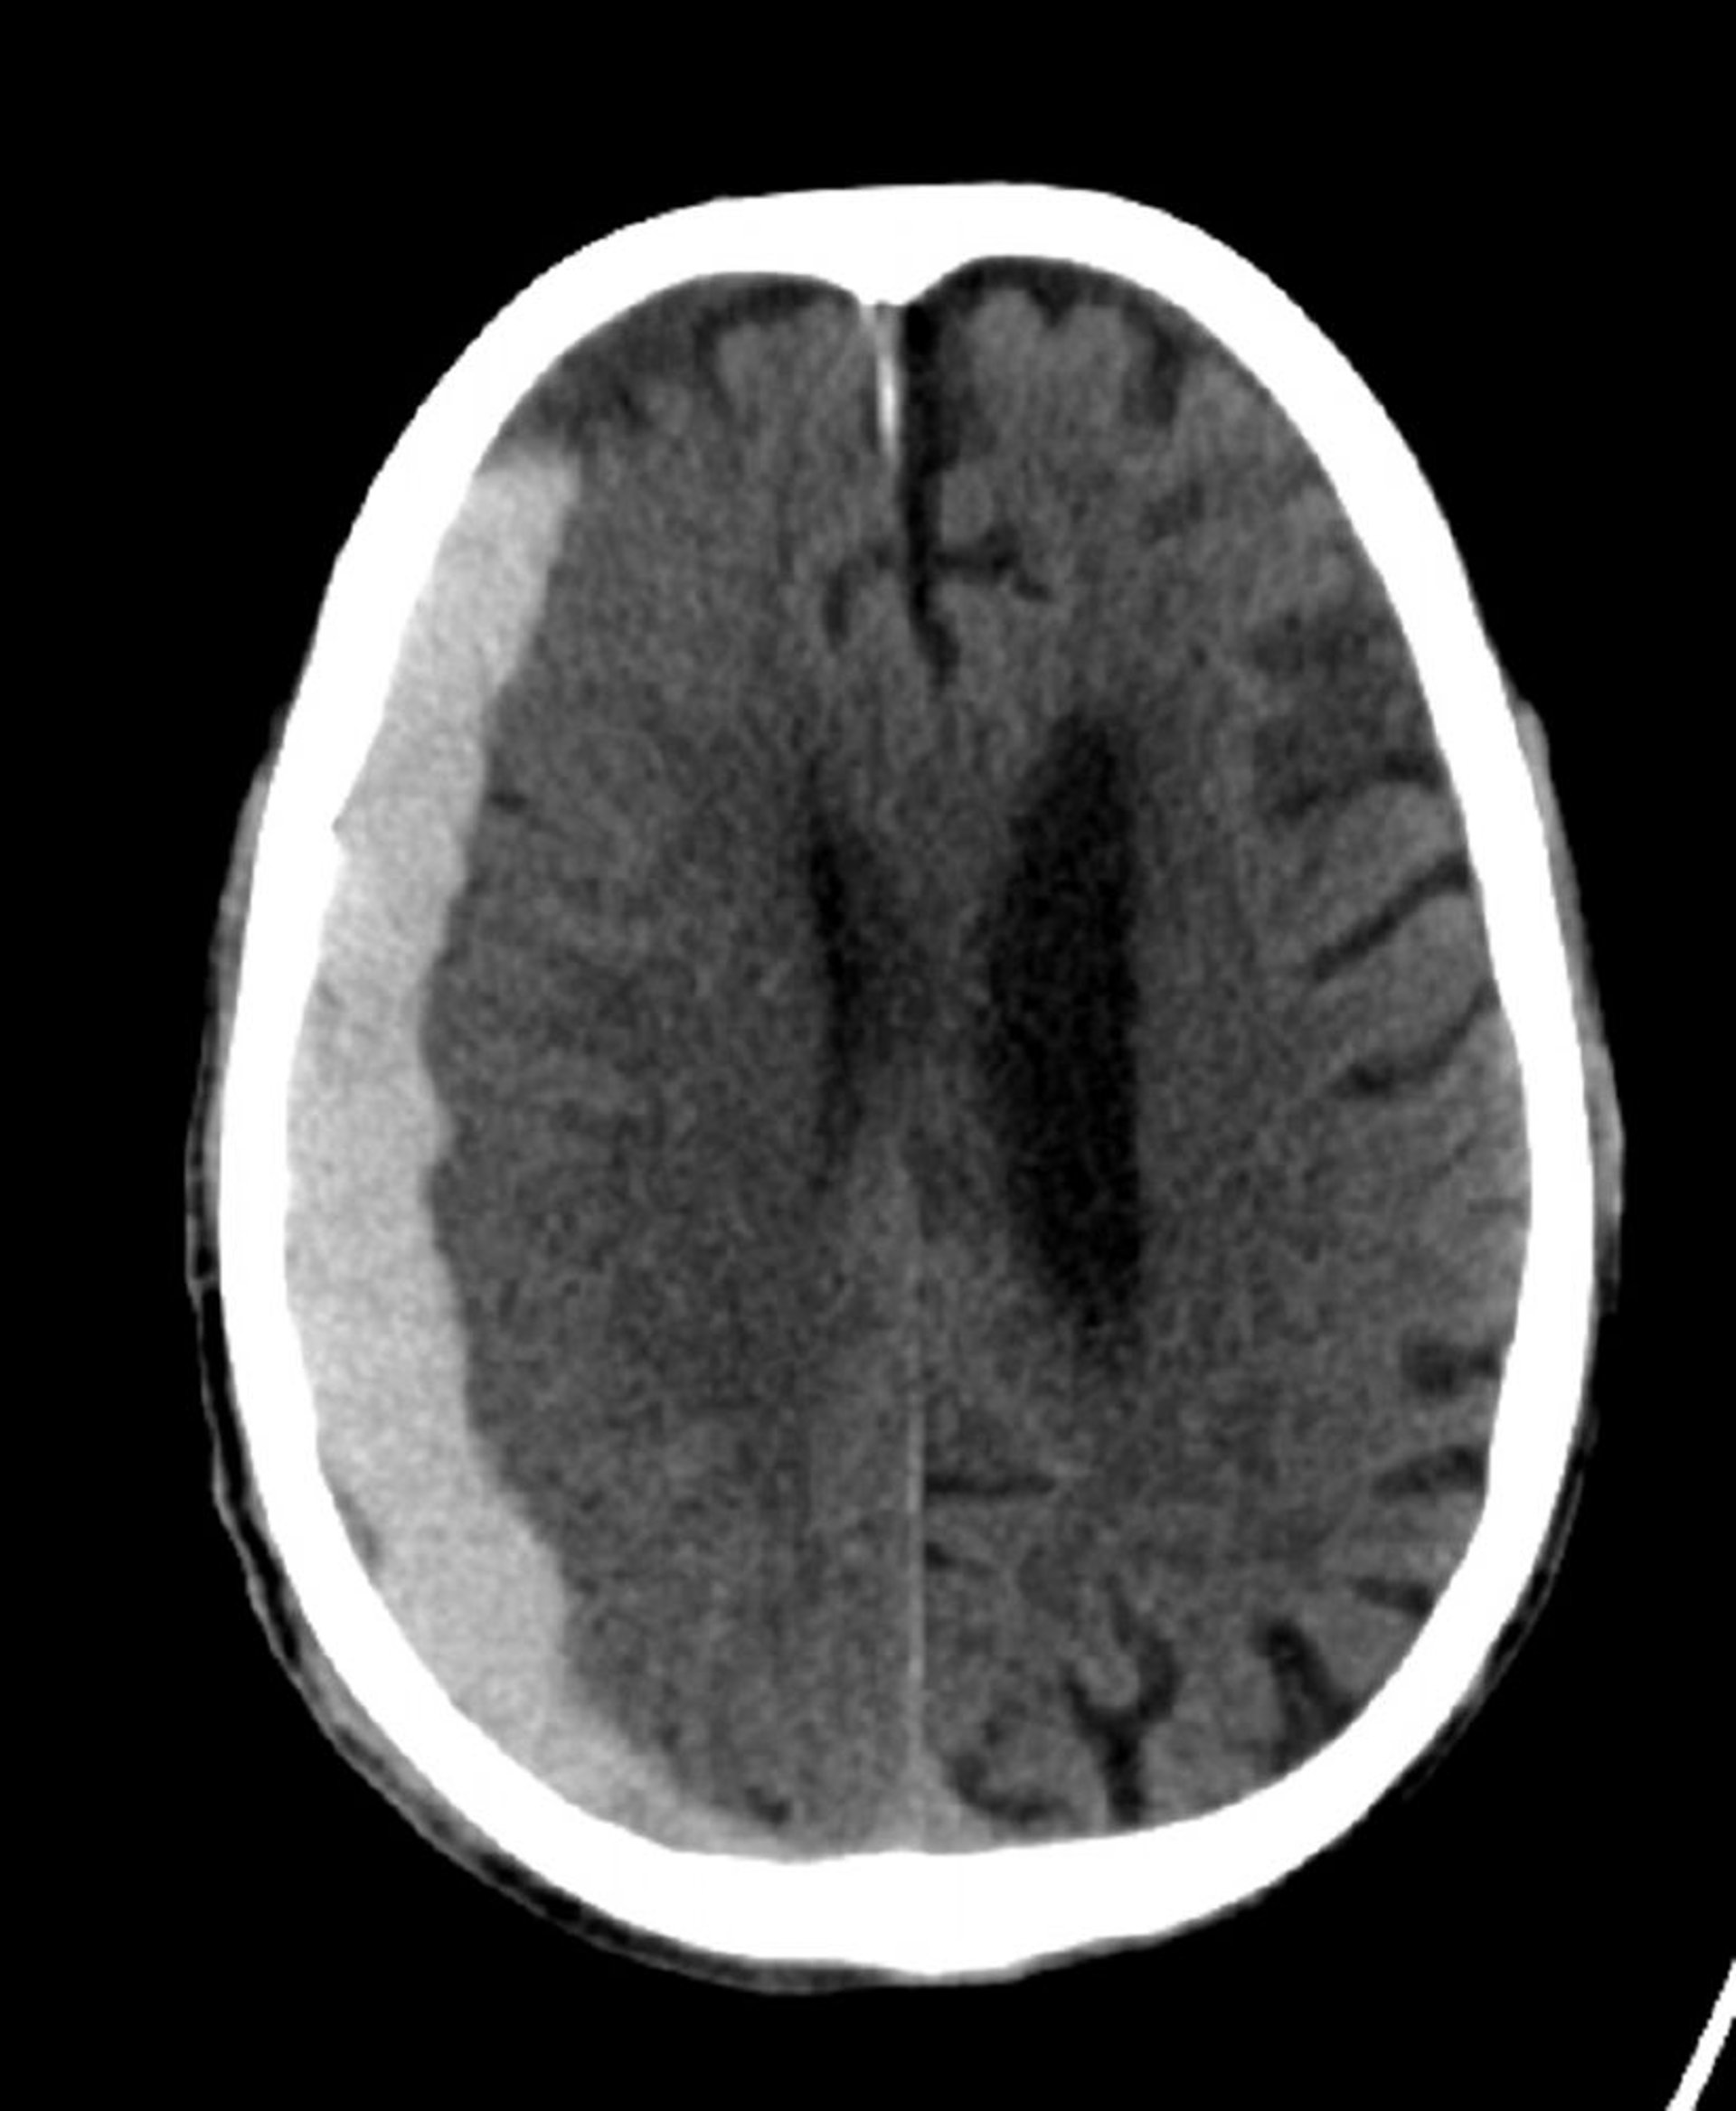

Emorragia subdurale (TC)

Iperdensità classica a forma di mezzaluna che si estende attraverso le linee di sutura.